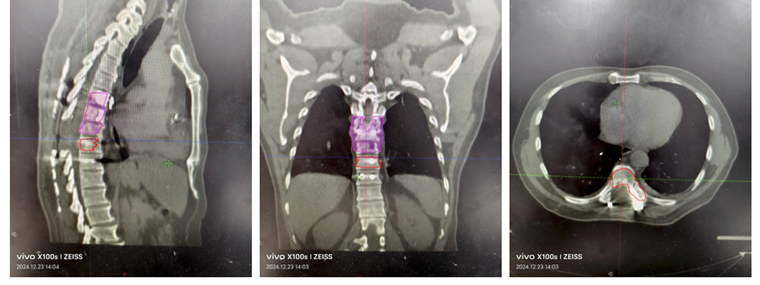

患者男性,62岁,半年前无明显诱因出现胸背部剧烈疼痛,伴下肢无力,严重影响了正常生活。就诊福建当地医院,胸部CT示:右肺下叶前基底段占位,右肺上叶后段类结节样影;T6-9椎体及部分附件多发骨质破坏。骨显像结果示:T6-9椎体显像剂摄取增高,考虑骨转移可能。遂于当地医院行肺部穿刺:(右下叶外基底段活检)结合免疫组化结果倾向腺癌。患者为行进一步治疗,至我院门诊收入病房。

1.T6-9胸椎继发恶性肿瘤(VAS 8分,SINS 11分, ESCC 1c,Tomita 6分,改良Tokuhashi 5分 )

2.肺腺癌(Ⅳ期,T4N1M1)

精准手术方案:后路减压固定+分离手术+病灶射频消融。患者为肺癌晚期,经影像学证实T6-9椎体呈现不同程度的骨质破坏。此次手术方案考虑到多个椎体的不同类型及不同程度的骨质破坏,特别是胸椎T8伴有压缩性骨折且侵犯椎管。通过仔细全面的术前评估,我们为患者制定了个性化的手术方案,对于T6、T7和T9椎体,采用了射频消融技术,精准靶向骨转移病灶,有效地控制了局部肿瘤进展,同时减少了不必要的组织损伤。对于T8椎体,考虑到压缩性骨折及椎管侵犯,我们进行了后路减压固定+分离手术,减轻了神经压迫,恢复了椎体稳定性,并配合椎体病灶消融,以确保治疗效果的最大化。这种精细化的手术方案,不仅充分处理了病灶,还最大程度减少了手术创伤,为患者提供了更为安全的治疗选择,术后恢复良好。

术后半年,患者按期进行了复查,胸椎的局部控制效果好,未见新的病灶出现,T8椎管未见明显狭窄,患者的疼痛症状持续缓解(VAS 3分)。更令人振奋的是,肺部原发病灶也有明显缩小,肿瘤负担大大减轻。患者表示,术后的疼痛得到了有效缓解,能够恢复正常的生活和工作,这使他重新找到了生活的希望。